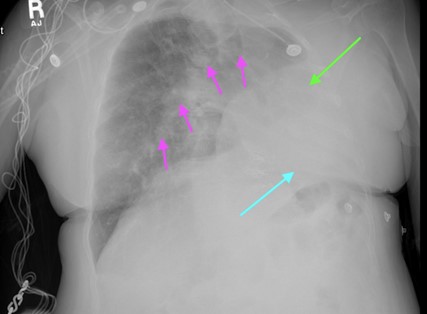

Chest radiography revealed diffuse bilateral interstitial prominence, left basilar consolidation, and a large left pleural effusion (Fig. 1). A non-contrast CT of the chest demonstrated severe emphysema with marked hyperexpansion of the right lung, near-complete destruction and volume loss of the left lung with mediastinal shift, and multiple calcified granulomas (Fig. 2). A 1.2-cm spiculated right lower-lobe pulmonary nodule was identified. CT of the head showed no acute abnormalities. Laboratory testing revealed no leukocytosis, but troponin levels were elevated (83.7→69 ng/L), consistent with type 2 myocardial injury. Serum bicarbonate was elevated (33–39 mEq/L), reflecting chronic CO₂ retention. Her hemoglobin decreased from 12.1 to 10.0 g/dL during hospitalization, and creatinine rose slightly from 0.94 to 1.12 mg/dL. Infectious studies, including a respiratory viral panel, were negative.

Figure 1: Xray Chest.

Arrows:

● Pink = Diffuse bilateral interstitial prominence

● Green = Large left pleural effusion

● Blue = Left basilar consolidation